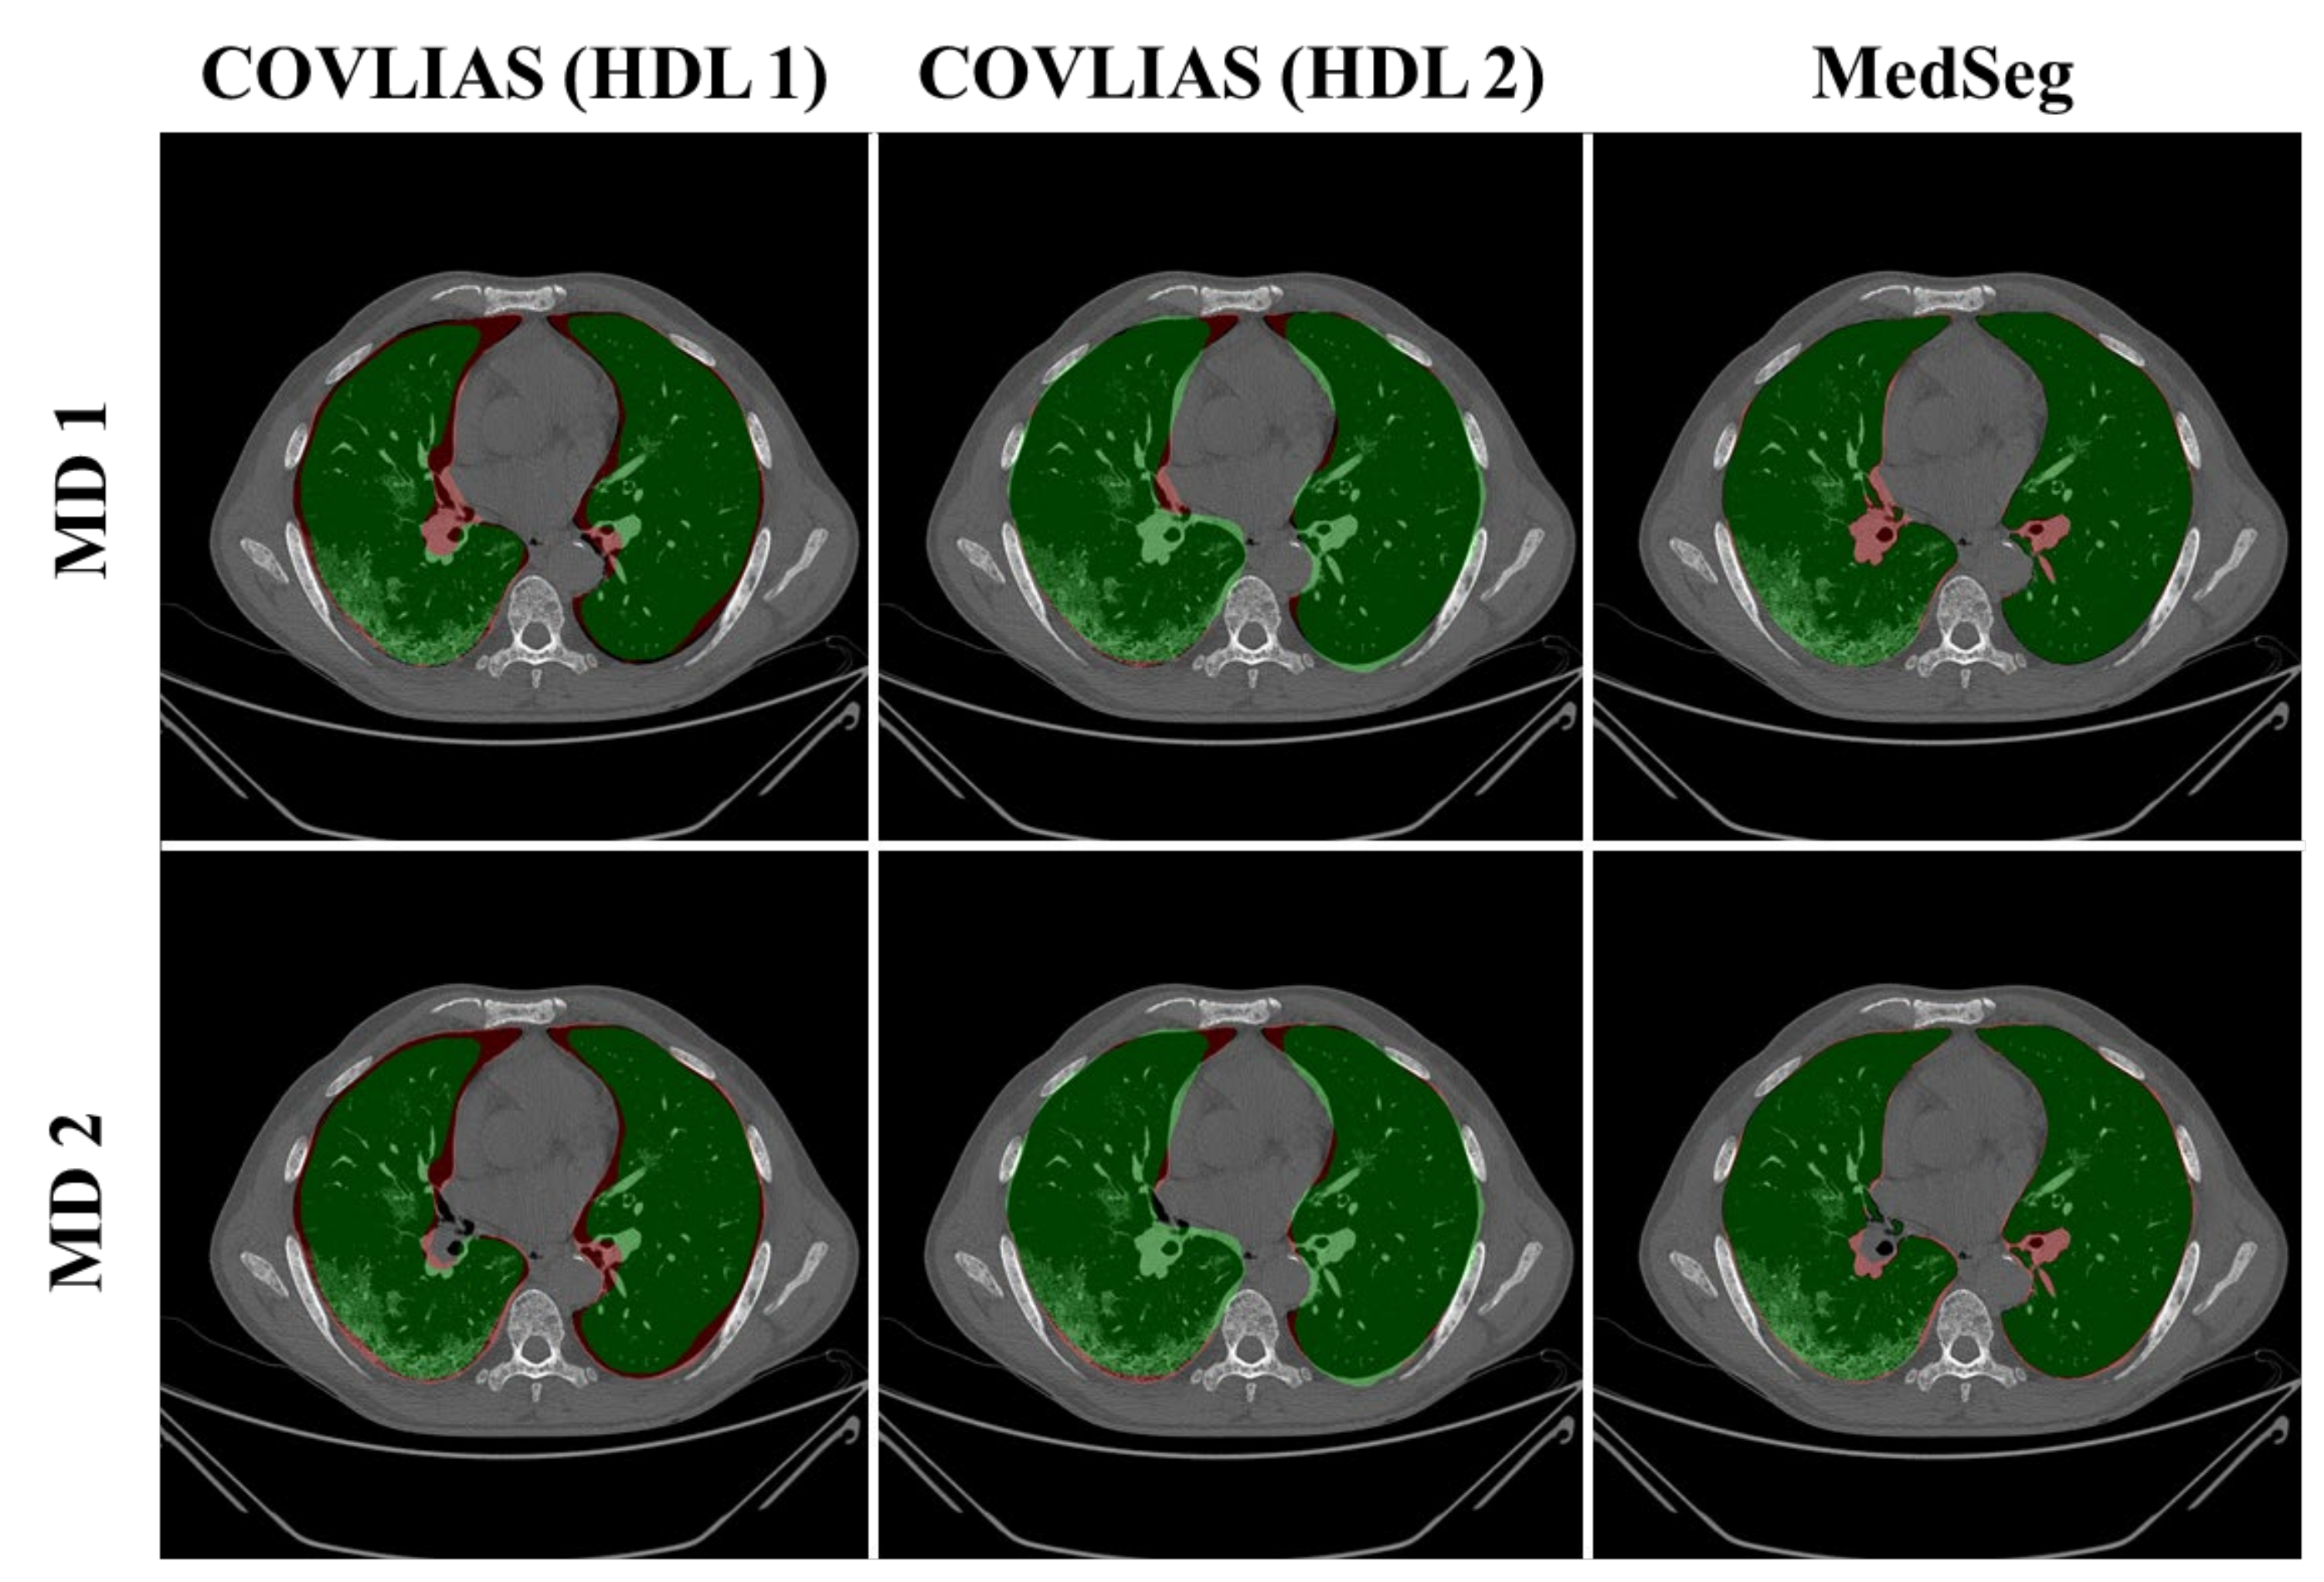

4.1. Performance: COVLIAS vs. MedSeg

| MD 1 | MD 2 | % Difference | |||||||

|---|---|---|---|---|---|---|---|---|---|

| Left | Right | Mean | Left | Right | Mean | Left | Right | Mean | |

| MedSeg | 96.42 | 96.85 | 96.61 | 96.36 | 96.55 | 96.45 | 0.1% | 0.3% | 0.2% |

| VGG-SegNet | 92.45 | 93.41 | 92.89 | 92.40 | 93.13 | 92.73 | 0.1% | 0.3% | 0.2% |

| ResNet-SegNet | 99.96 | 98.63 | 99.39 | 99.98 | 98.30 | 99.23 | 0.0% | 0.3% | 0.2% |